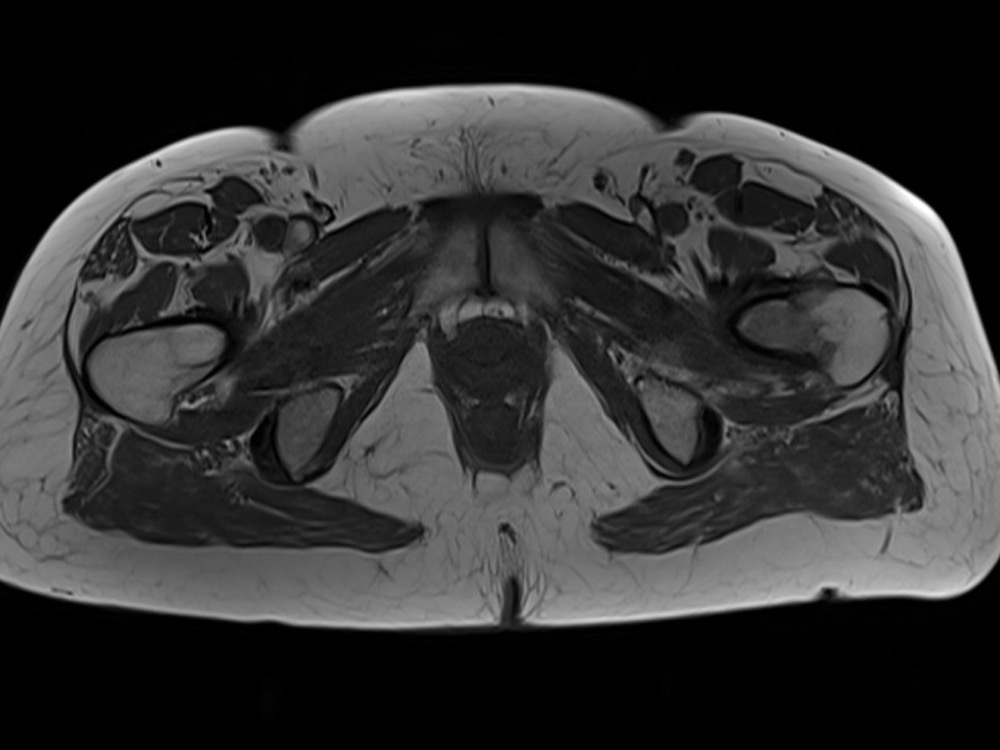

Douleurs de hanche

Linda Ouerd 06/11/2019